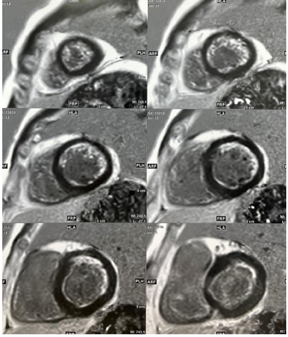

心脏核磁平扫印象:左室心尖部略薄,必要时可对比增强扫描评估心肌组织学特性(图14)。

心脏常规MRI示:左房、左室不大;左室心尖部变薄,余左室各节段室壁厚度正常,左室前壁、侧壁中远段T2信号升高,考虑存在心肌水肿信号;左室收缩及舒张运动大致正常,左室流出道通畅。右房不大,右室饱满,右室壁未见脂肪浸润信号。房室瓣及主动脉瓣启闭正常。心包无增厚。

心肌首过灌注未见明确减低或缺损,延迟扫描可见左室前壁、侧壁中远段及心尖部可见心内膜下强化,侧壁及心尖部肌小梁不规则强化。

心脏核磁增强印象:冠心病急性心肌梗死(心内膜下为主),主要累及左冠状动脉供应区域,左室整体收缩功能正常范围(图15)。

1.心肌活力评价:心尖部心肌存活(冬眠心肌占左心室的7%);其余心肌节段血流灌注/代谢正常。2.左室功能评价:左室心腔略增大,心尖部运动减弱,左心射血分数:60%(图16)。